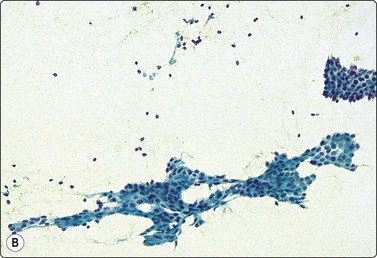

image image

Fig. 7.2 Non-neoplastic glandular breast tissue and low-grade duct carcinoma

Low-power view; (A) Bimodal population of epithelial sheets and single bipolar nuclei of non-neoplastic glandular breast tissue; (B) Single population of epithelial cells in low-grade carcinoma (MGG, LP).

Fig. 7.3 Non-neoplastic glandular breast tissue and low-grade duct carcinoma

High-power view, air-dried smears; (A) Non-neoplastic glandular breast tissue; (B) Low-grade duct carcinoma. Note single bipolar nuclei in A, and absence of bipolar nuclei, relatively mild nuclear atypia and some loss of cohesion of malignant cells in B (MGG, HP).

Fig. 7.4 Non-neoplastic glandular breast tissue and low-grade duct carcinoma

High-power view, Pap-stained smears; (A) Bimodal population in smear from non-neoplastic breast; (B) Single and clustered cells in low-grade carcinoma; some single cells probably stromal (Pap, HP).